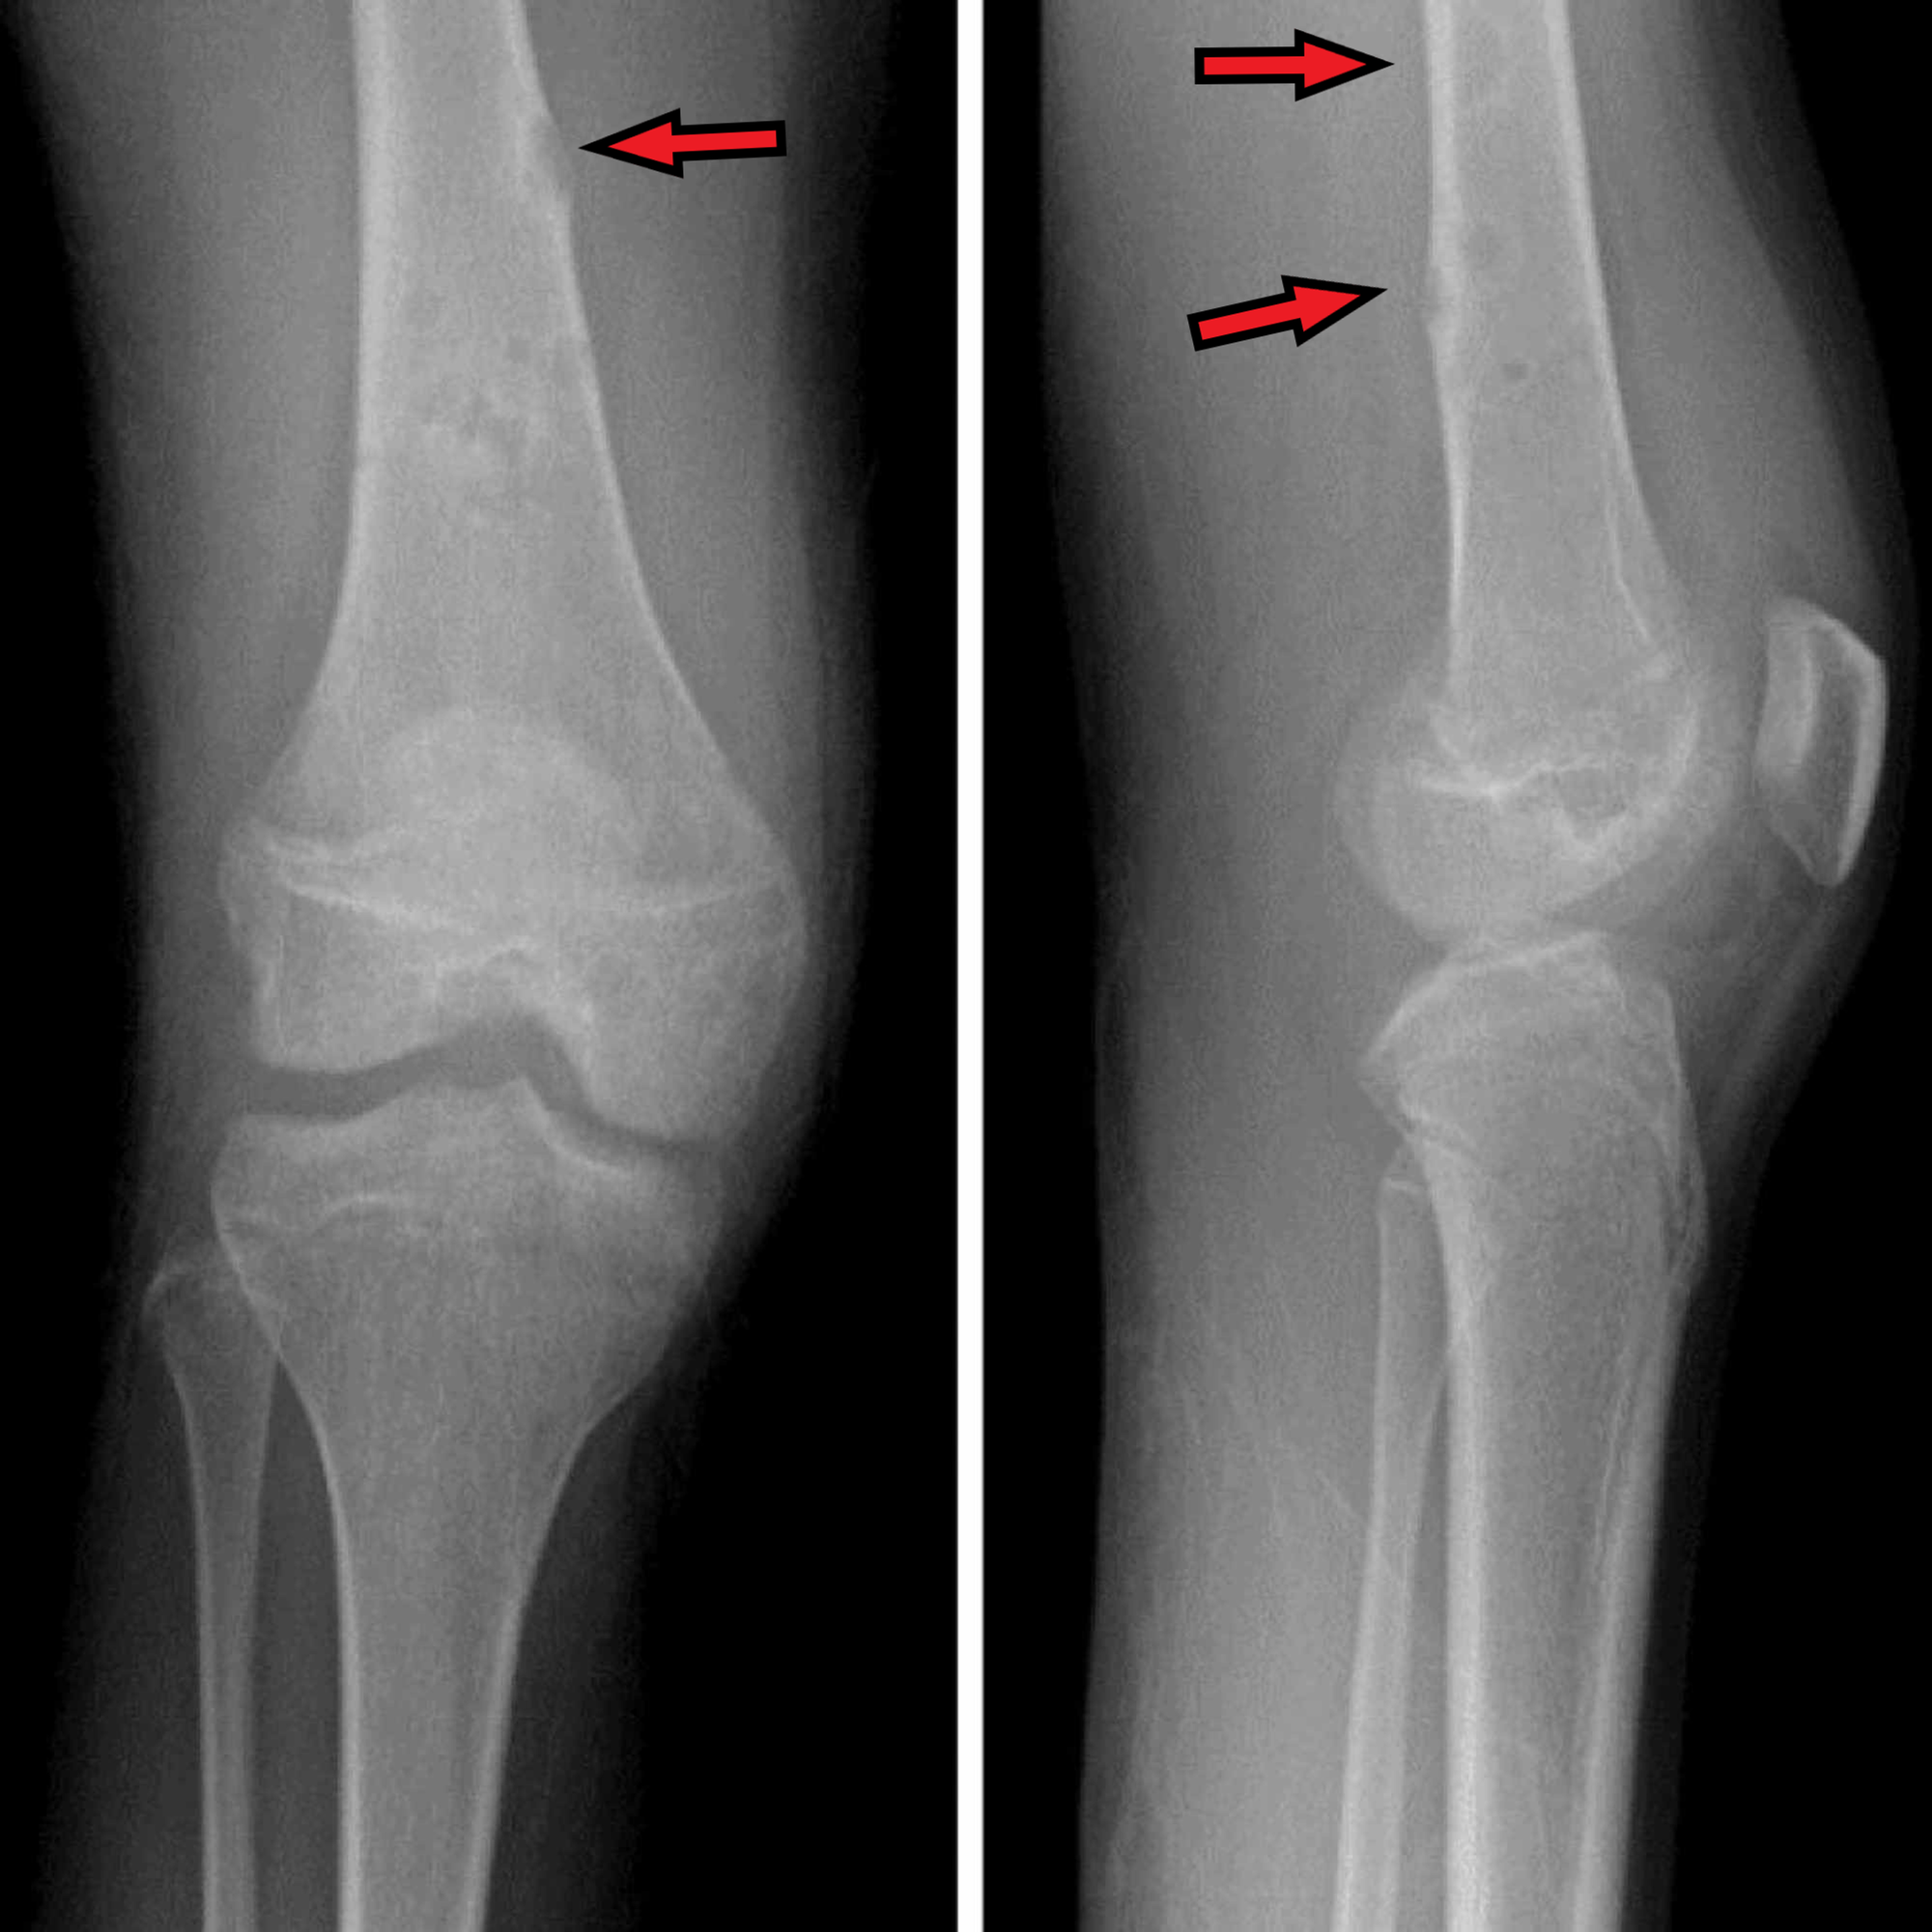

MRI of the right knee showed scattered enhancing areas of marrow edema and cystic changes involving the right distal femoral diaphysis, metaphysis, and epiphysis (Figure 2). Also, there was extensive cellulitis and myositis surrounding the right knee and extended proximally to the level of the greater trochanter with small developing organized fluid collections within the proximal vastus lateralis and intermedius muscles, representing evolving abscesses.